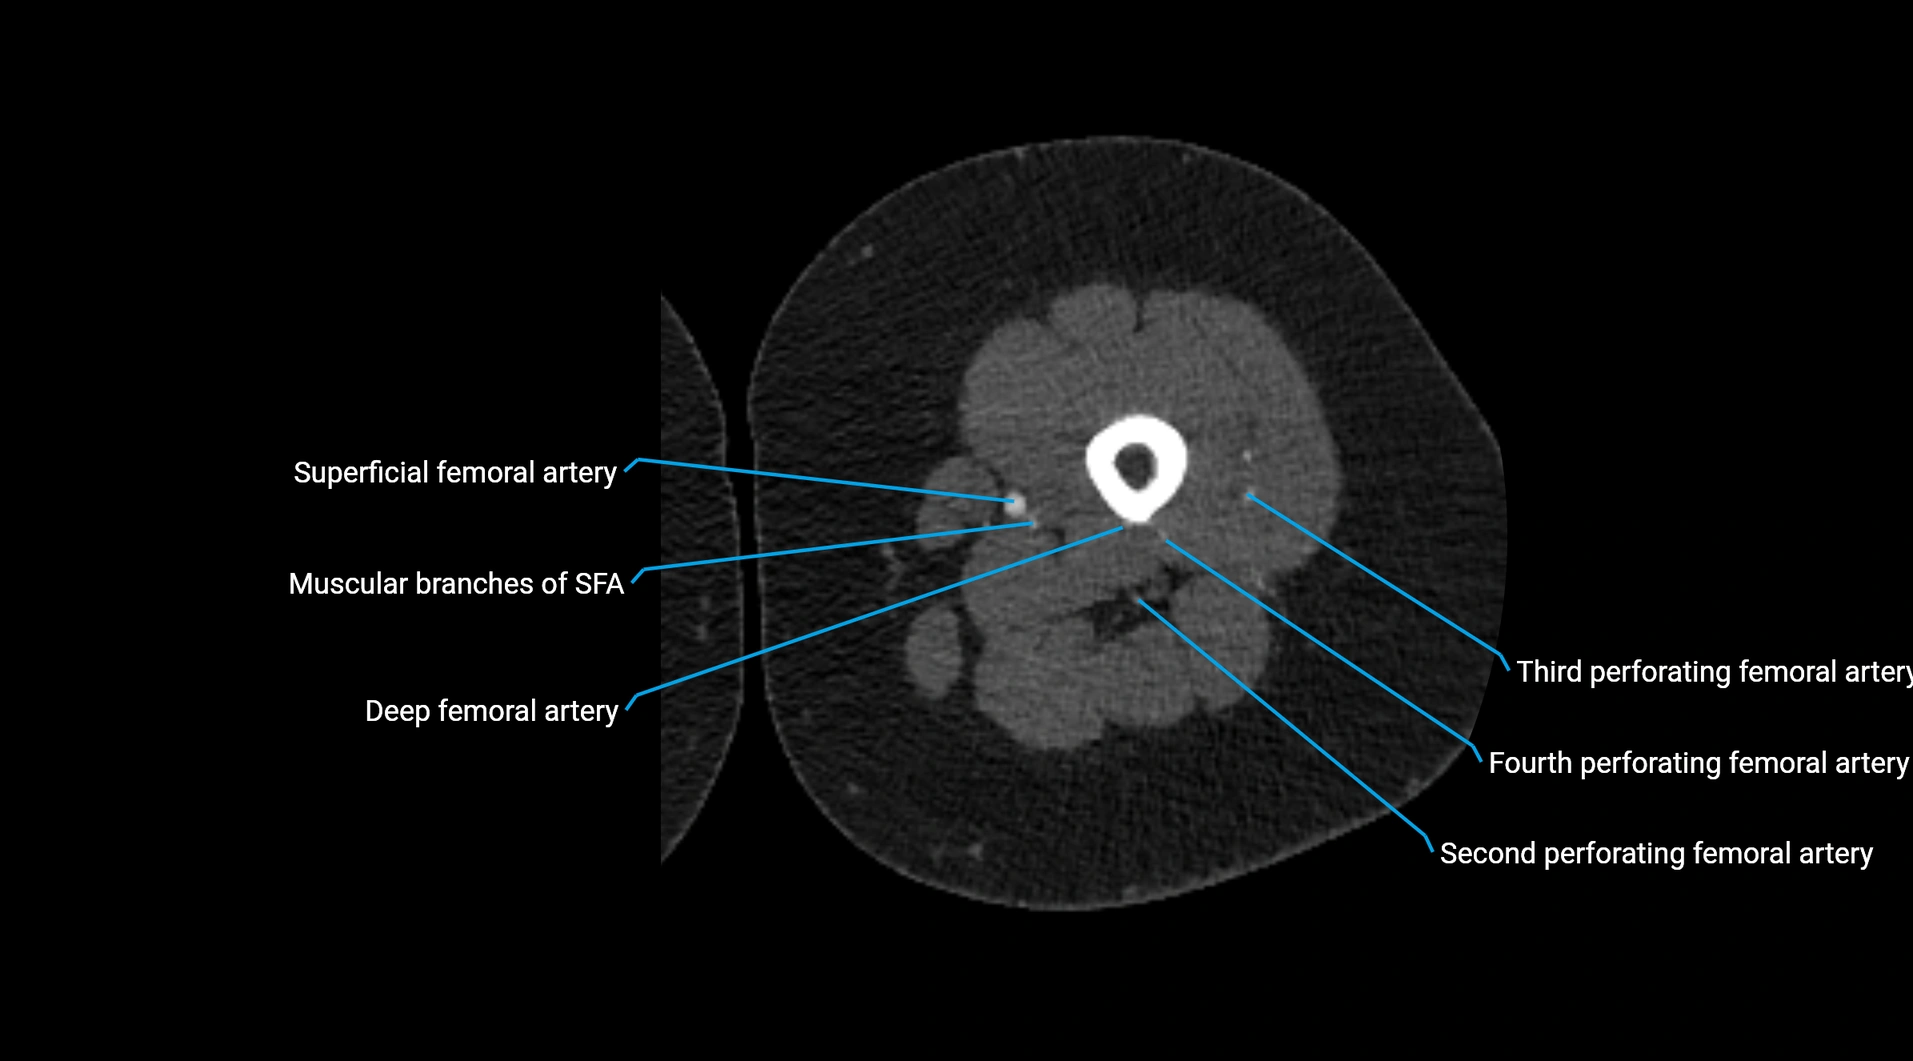

Contrast-enhanced CT (CTA):

• Gold standard for abdominal aortic imaging

• Provides excellent detail of lumen, wall, aneurysm, thrombus, and branch vessels

• Multiplanar and 3D reconstructions help in aneurysm measurement, stent graft planning, and dissection evaluation

• Detects acute rupture, traumatic injury, or occlusion with high sensitivity